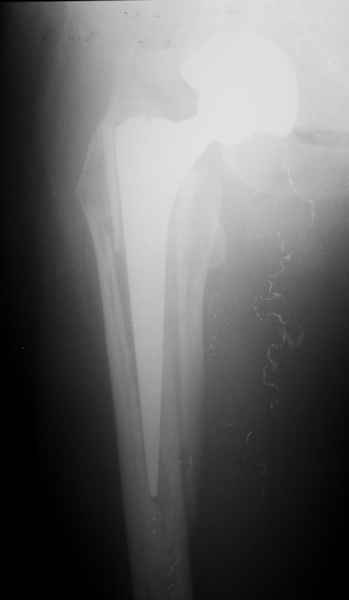

Закрытый остеосинтез-удлинение ножки (подход далеко не общепринятый, и пока даже не общеизвестный)- наименее инвазивный вариант, который обеспечивает немедленное восстановление опороспособности. Конечно, хотелось бы, чтобы эта операция решила проблему окончательно, т.е. в

ближайшие годы других больших операций не потребовалось бы.

ножка просела немного (вопрос, много - это сколько?)перечисленные проблемы - не самое важное сейчас, на них можно закрыть глаза. Ножка явно нестабильна, проксимальный отломок с б/вертелом к гвоздю не прицепить, срастется ли он с ножкой

1.Остеосинтез на ножке. Мне кажется, что применительно к этому случаю малоперспективный вариант. Синтез хорош, когда можно его выполнить в малоинвазивном исполнении и достигнуть стабильности. Действительно, если ножка б/цементной фиксации после этого не будет иметь фиксации, то ревизия не будет иметь проблем. В представленном случае стабильность синтеза сомнительная, а проведение доп.иммобилизации приведет к контрактуре суставов.